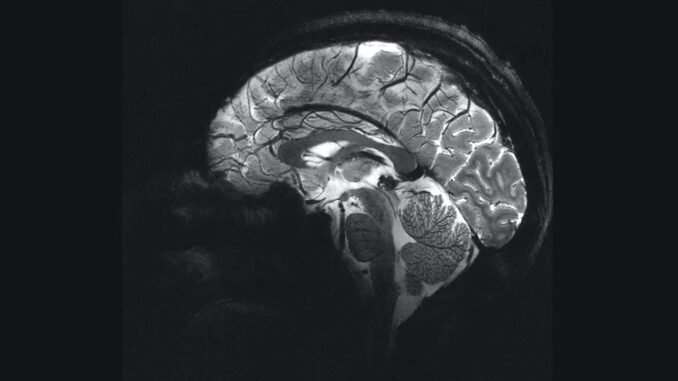

Dünyanın En Güçlü Manyetik Rezonans Görüntüleme Cihazı

Dünyanın en güçlü manyetik rezonans görüntüleme (MR) cihazı, ortalama bir hastane tarayıcısının saatlerce çalışmasını gerektirecek bir çözünürlüğe yalnızca dört dakikada ulaşabilmektedir. Bu cihaz, bilim insanlarına insan beynine benzersiz bir pencere açarak önemli bir katkıda bulunmaktadır.

Şimdi ise, Iseult MR makinesi adı verilen yeni nesil bir cihaz, 11,7 T güce ulaşarak dikkatleri üzerine çekmektedir. Bu olağanüstü güç, yayınlanan beyin görüntülerinin kalitesini de gözler önüne sermektedir. Pratikte, bu yüksek çözünürlük, 1,5 veya 3T tarayıcıların alacağı görüntüleri çok daha kısa sürede elde edebilmek anlamına geliyor.